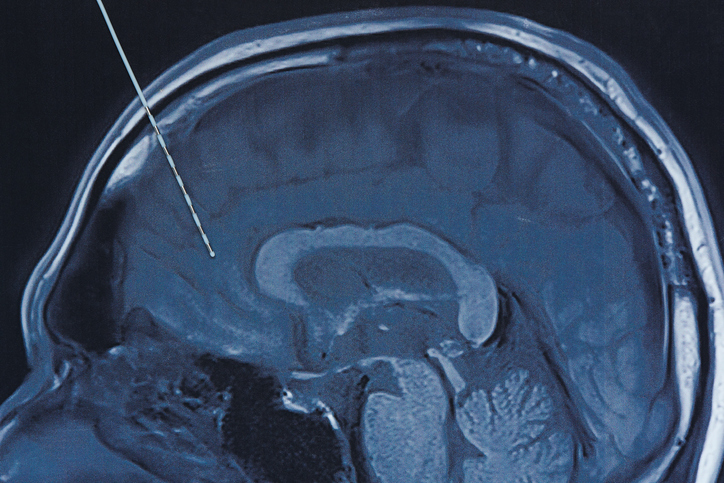

El multimillonario Elon Musk ha afirmado a traves de la red social X (antes Twitter) de su propiedad que ha implantado por primera vez con exito en humanos uno de los implantes cerebrales inalambricos de su compañia Neuralink. Segun explico, los resultados iniciales han mostrado una deteccion prometedora de los picos en la actividad neuronal.

“Es simplemente un reporte de progreso del testeo de dos cosas: un implante (lo que Musk llama chip) y del robot quirurgico que lo inserta en el cerebro humano”, desarrolla para 20minutos Liset Menendez de la Prida, investigadora del CSIC y directora del Laboratorio de circuitos neuronales del Instituto Cajal.

Tal y como apunta Ezpeleta, hay que entender el funcionamiento basico de estas: “Las interfaces cerebro-computador lo que hacen es leer las señales electricas de la zona del cerebro en la que se inserta el sensor, la analizan y dependiendo del sistema de Inteligencia Artificial empleado la interpretan para que desencadene una accion determinada, como mover un cursor en una pantalla o accionar un brazo mecanico”.

“Una de las cosas que caracteriza el dispositivo de Neuralink”, desarrolla por su lado De la Prida, “es la miniaturizacion de todos los componentes. Esto es importante; la capacidad de insertar muchos sensores en un aparato pequeño que ademas es bueno a la hora de transmitir la señal de manera inalambrica contribuye a hacer mucho mas viable el implante”.

“Y por lo que he podido ver, se intuye que estan generando algoritmos de procesamiento que deben ser muy eficientes en algunos sentidos, de acuerdo con lo poco que se ha conocido”, sigue, “y tienen un robot quirurgico que tambien les diferencia y que permite el implante de los electrodos uno a uno, garantizando una mejor respuesta del cerebro al implante.